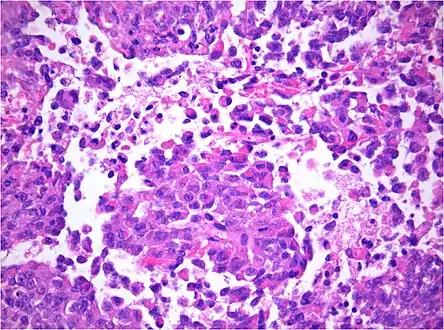

AT/RT and rhabdoid tumor share the term "rhabdoid" because under a microscope, both tumors resemble rhabdomyosarcoma.

AT/RT Histology with numerous rhabdoid tumor cells

Rhabdoid Tumor Cell - 400X Magnification

Histology

The tumor histopathology is jumbled small and large cells. The tissue of this tumor contains many different types of cells including the rhabdoid cells, large spindled cells, epithelial and mesenchymal cells, and areas resembling primitive neuroectodermal tumor (PNET). As much as 70% of the tumor may be made up of PNET-like cells. Ultrastructure characteristic whorls of intermediate filaments are seen in the rhabdoid tumors (as with rhabdoid tumors in any area of the body). Ho and associates found sickle-shaped embracing cells, previously unreported, in all of 11 cases of AT/RT.[18]